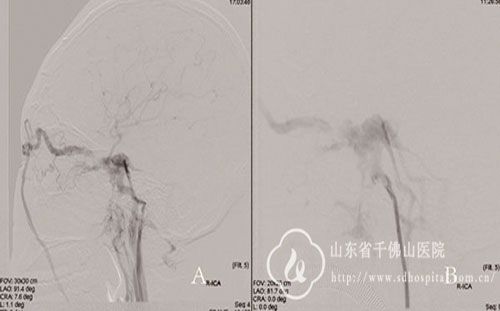

急症造影证实为右侧颈内动脉海绵窦瘘A型,同时造影显示健侧颈内动脉及后循环分别通过前交通、右侧后交通动脉供应右侧颈内动脉远侧供血区,而患侧颈内动脉自身的正向血流已明显减少。

随后将一枚4.5*16mm Willis支架成功置入,造影结果见支架贴敷良好,患侧颈内动脉通畅,颈内动脉海绵窦瘘完全消。术后患者颅内杂音消失,右眼肿胀日渐减轻,病情恢复良好顺利出院。